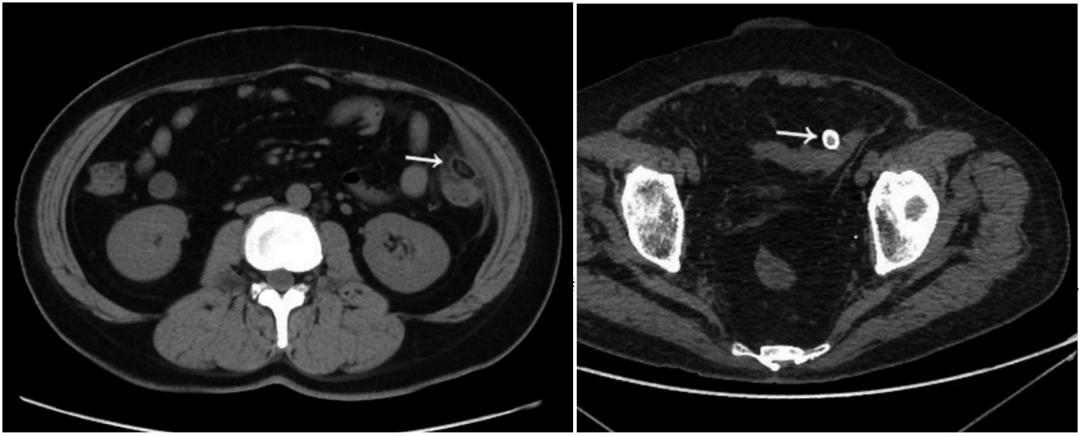

患者,男性,44岁。乙状结肠肠脂垂炎。平扫轴位示乙状结肠近端旁见一直径约11mm稍高密度环影(白线所指处),环壁厚约1.9mm,中央区见点状高密度影。

患者,女性,50岁。乙状结肠肠脂垂炎。CT平扫轴位示乙状结肠旁见一直径约10mm稍高密度环影,环壁厚约2.0mm,稍高密度环影与肠壁间见狭窄的短蒂相连。